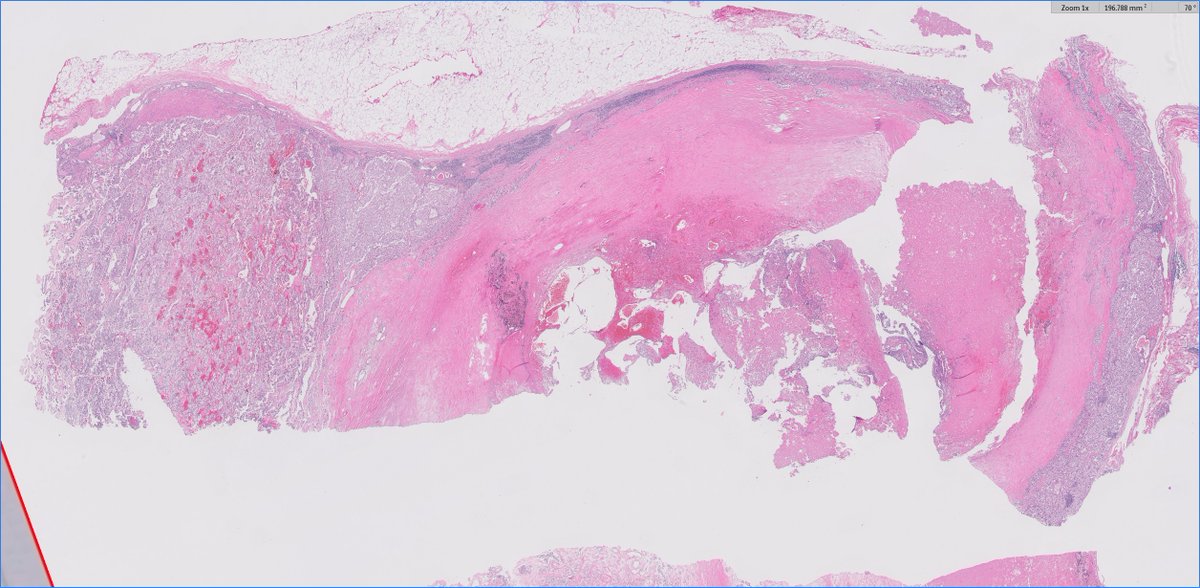

@skipocytes

Pathologist. Cases posted for interest and education with the pathology community, everything else sarcasm/humor. And the gifs. Oh, the gifs.